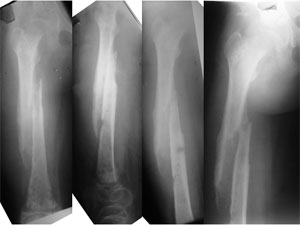

| Post Operative X-rays |

| The post-op x-rays showing the position of the antibiotic cement rod & beads. The fracture has been reduced after removal of the dead bone and tissue. The nail end in the lower portion of femur is just proximal to the growth plate. |

| The x-rays at 2 months after surgery show good progress of healing, resolution of the infection completely and improvement in the quality of the overall bone. The screws in the neck of the femur were applied because she developed a slipped capital femoral epiphysis (slippage of the growth plate of hip joint ball). |

| 5 Months Post Op |

| The X-ray pictures 5 months after the surgery. These were actually taken prior to removal of the antibiotic cement beads. The fractures have healed well, the infection is also settled, with no signs of recurrence and no signs of loosening of the implants. |